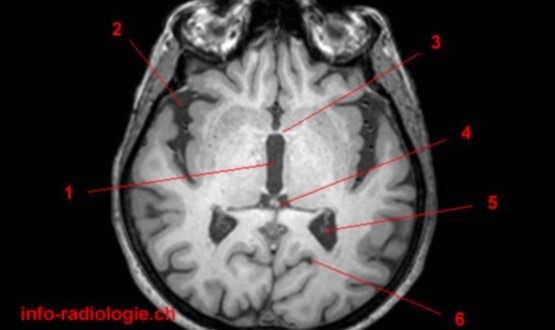

Label 1-6

Label 1,3,4,5,7

1=3rd ventricle

3-Anterior commissure

4=Pineal gland

5=Choroid plexus

7=Posterior commissure

Label 4,5,6,8,9

4=Genu, CC

5=Lt lateral ventricle (body)

6=Head of Rt caudate nucleus

8-Rt Lentiform nucleus

9=Lt lateral ventricle (post. horn)

Label 2,18,19,21

2=Rt internal capsule

18=Frontal sinus

19=Septum pellucidum

21=Lt external capsule